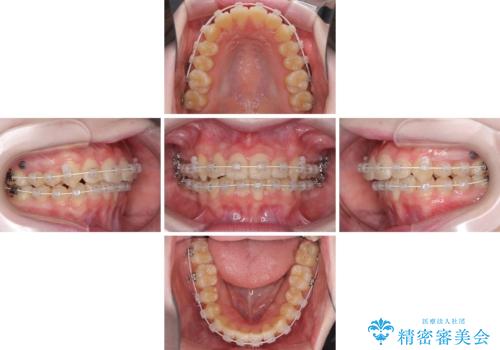

- 矯正装置

- 審美装置

- 1年10ヶ月

- 10-30回